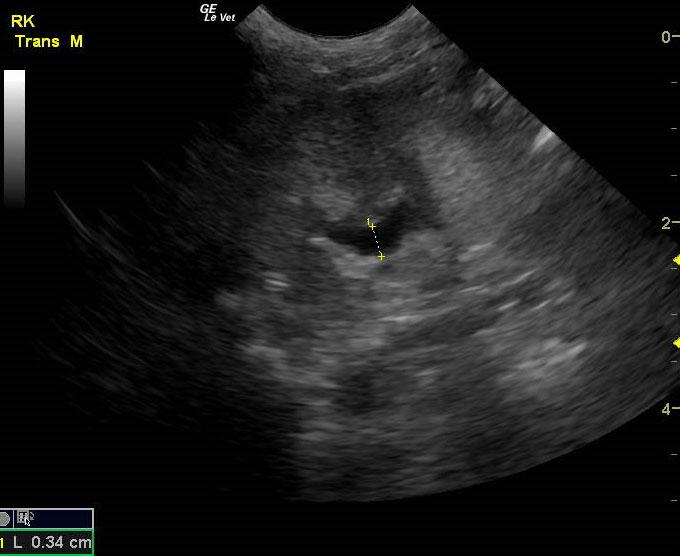

A 14-year-old neutered male Pomeranian dog was presented for evaluation of pollakiuria, diarrhea, inappetence, and lethargy. Abnormalities on physical examination included a painful, enlarged and symmetrical prostate, a very large and firm urinary bladder that could be expressed, and a grade III/VI heart murmur. On survey thoracic radiographs, calcification of the prostate gland was evident.

A 14-year-old neutered male Pomeranian dog was presented for evaluation of pollakiuria, diarrhea, inappetence, and lethargy. Abnormalities on physical examination included a painful, enlarged and symmetrical prostate, a very large and firm urinary bladder that could be expressed, and a grade III/VI heart murmur. On survey thoracic radiographs, calcification of the prostate gland was evident.